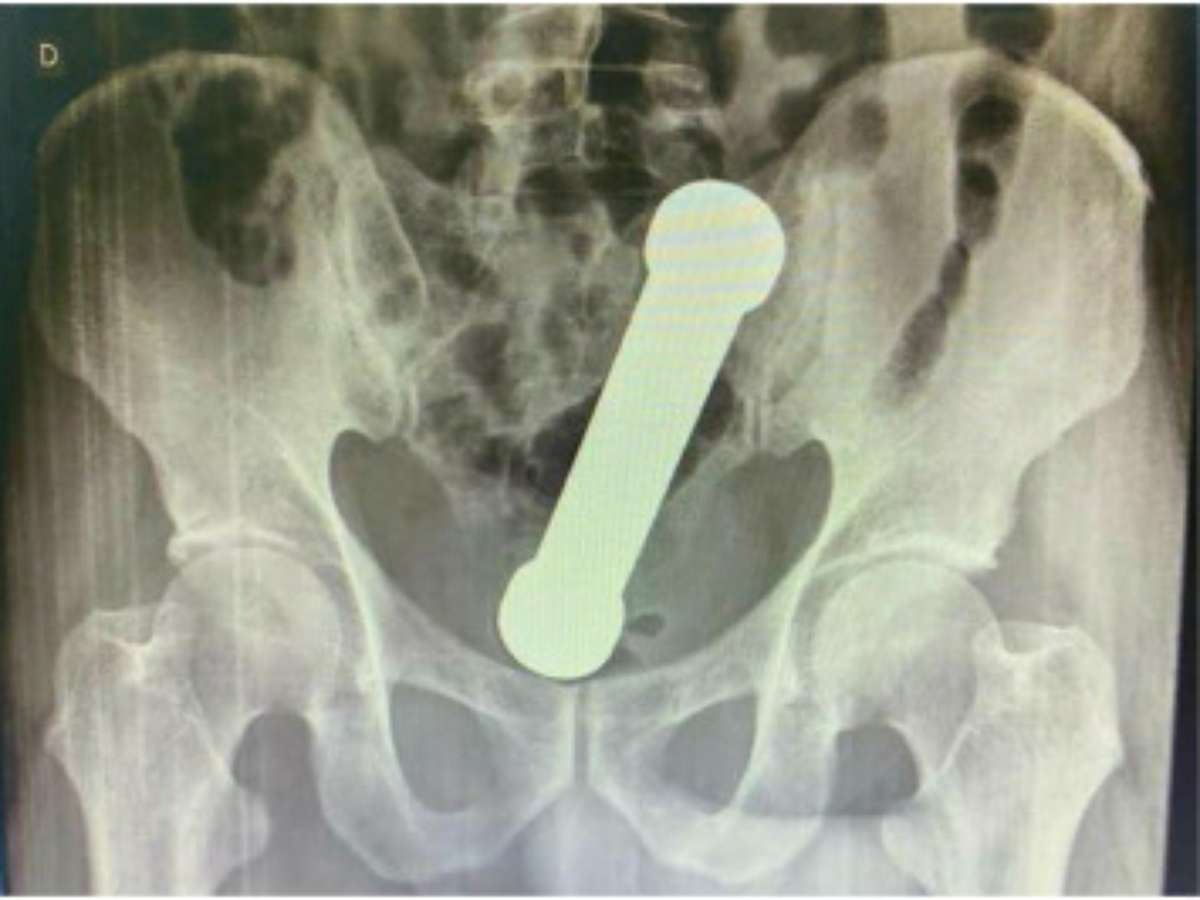

Foto: International Journal of Surgery Case Reports

Os médicos solicitaram exames para descobrir a origem do problema e se surpreenderam com as imagens de radiografia, que revelaram um halter, aquele peso de mão usado em academias, dentro do corpo do paciente.

O objeto tinha 20 centímetros e dois quilos. Foi necessário um procedimento cirúrgico para anestesiar o homem e poder retirar o halter de seu corpo. A cirurgia foi bem sucedida e o paciente recebeu alta após três dias internado.

O episódio foi descrito na International Journal of Surgery Case Reports com o título ”manejo de incomum corpo estranho retal” e com algumas fotos para ilustrar a excepcionalidade do caso.